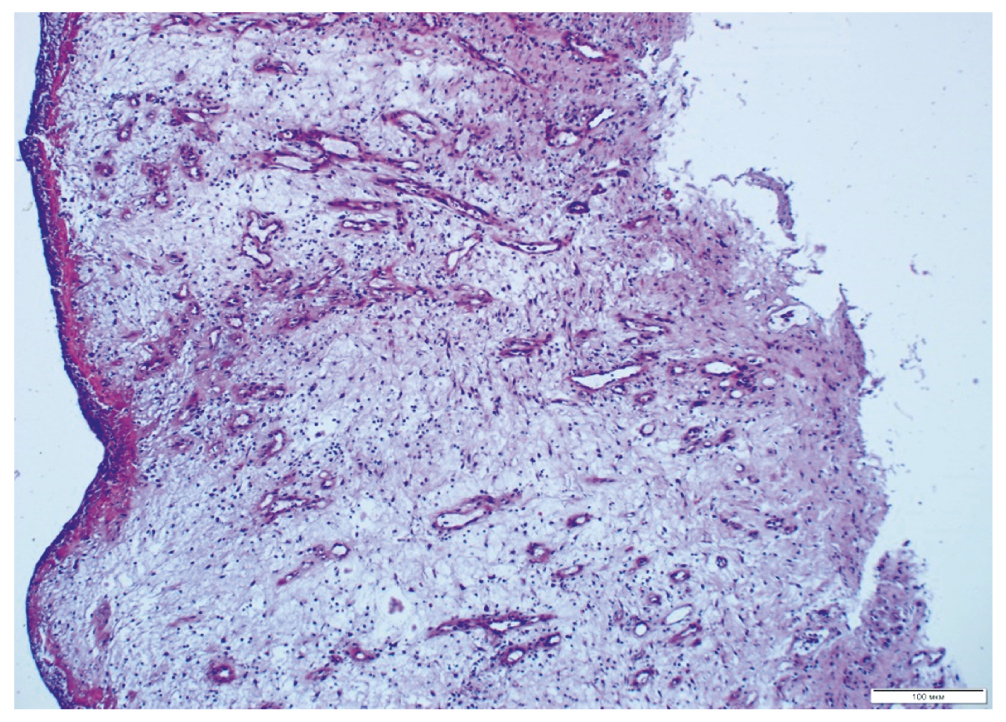

Изначально все пролежни имели вид открытых длительно незаживающих язвенно-некротических дефектов с выраженной воспалительной реакцией и очевидной стагнацией РП: налёты фибрина, очаги некроза, редкие локусы вялых грануляций, отёчные ригидные края, отсутствие краевой эпителизации, экссудация и т.п. При гистологическом исследовании биоптатов в препаратах краёв ДЯ в обеих группах отмечена зона фибриноидно-некротических изменений с подлежащим слоем незначительно выраженной грануляционной ткани, наблюдались явления отёка межуточной ткани, рассеянная инфильтрация полиморфно-ядерными лейкоцитами с примесью эозинофилов (рис. 2).

Рис. 2. Биоптат ткани дна пролежня перед началом лечения. Окраска гематоксилином и эозином.

Fig. 2. Biopsy of the bottom tissue of the bedsore before treatment. Stained with hematoxylin and eosin.

Новообразованных сосудов капиллярного типа не наблюдалось.